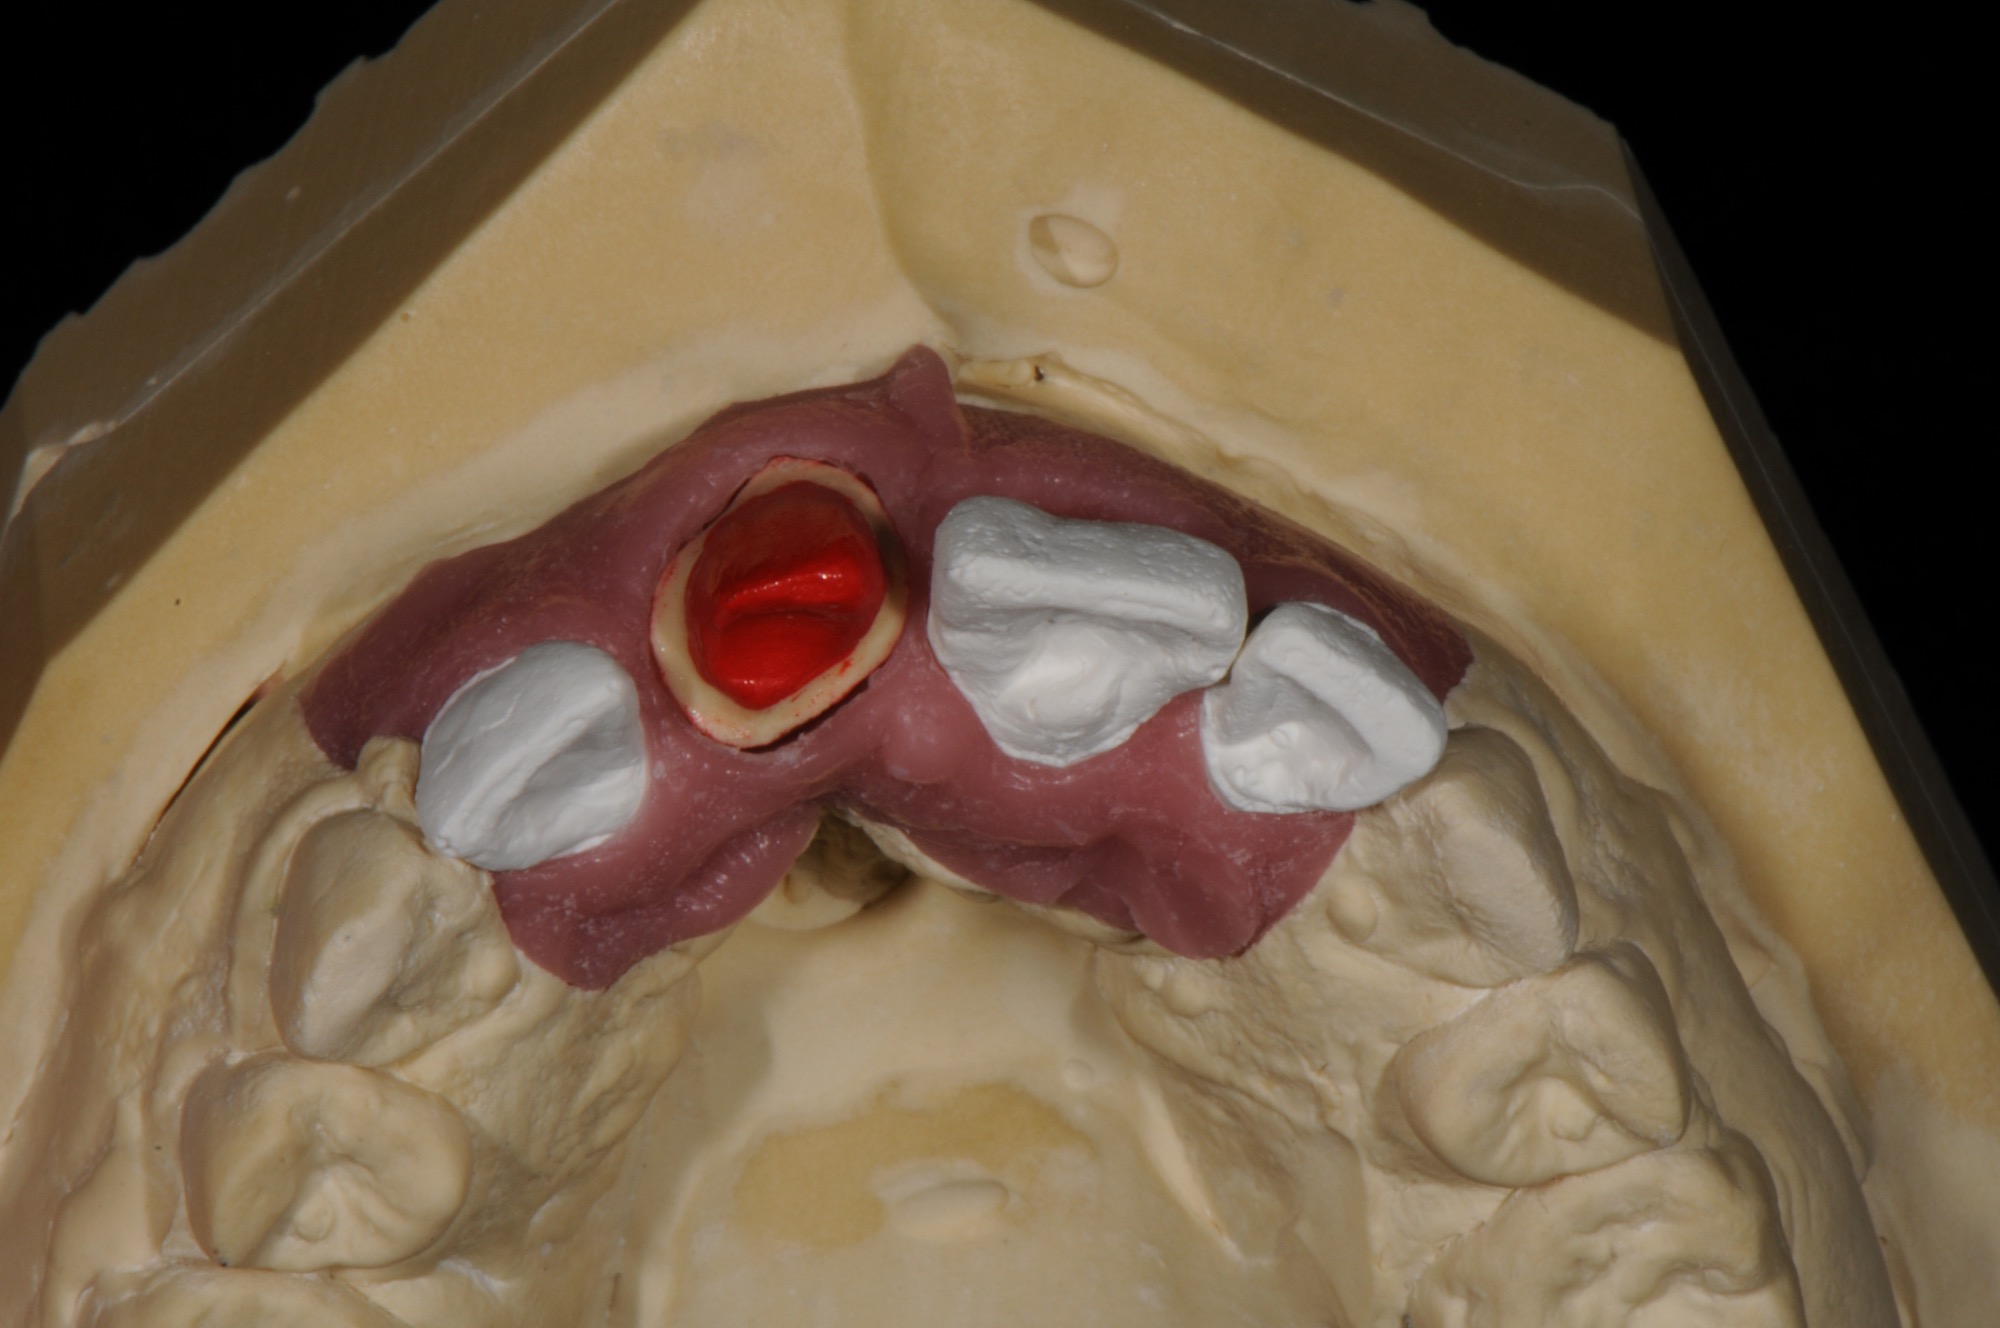

Virtuelle Planung mit Vorab-Provisorium aus dem Labor.

Der Monoreduktor stellt eine implantatfreie Alternative für einen zahnlosen Bereich in Kombination mit einer mindestens dreigliedrigen Kronenversorgung dar.